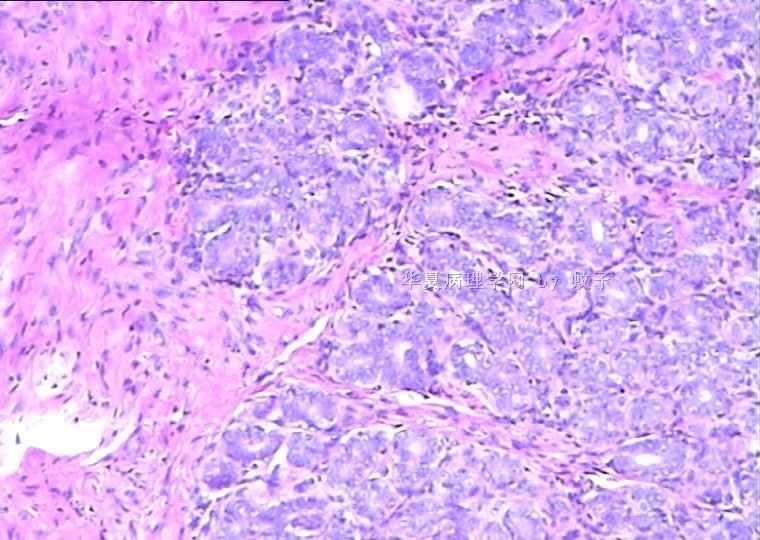

B2156乳腺活检

姓    名: ××× 性别:  女 年龄:  20

简要病史:  右乳包块8年。

肉眼检查:  灰白不整形组织一块,切面灰白,灰红,实性,质韧。

• 乳腺活检图1

图1

标签:乳腺腺病

旺识型腺病

有包膜吗?良性,首先考虑纤维腺瘤(图5、6透明变的纤维支持),其次腺瘤。

无明显包膜,界限较清,

我们考虑腺瘤,(图5,6为混有纤维瘤组织)

腺病瘤(主要成份旺炽性腺病)部分区域为纤维腺瘤(管内型)